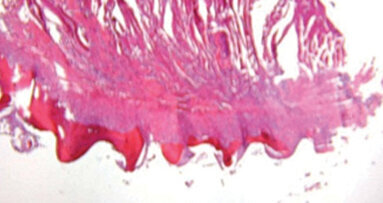

Dental fluorosis is an enamel anomaly that adversely affects inorganic phase deposition and organisation, causing enamel hypomineralisation.1 Despite the ...